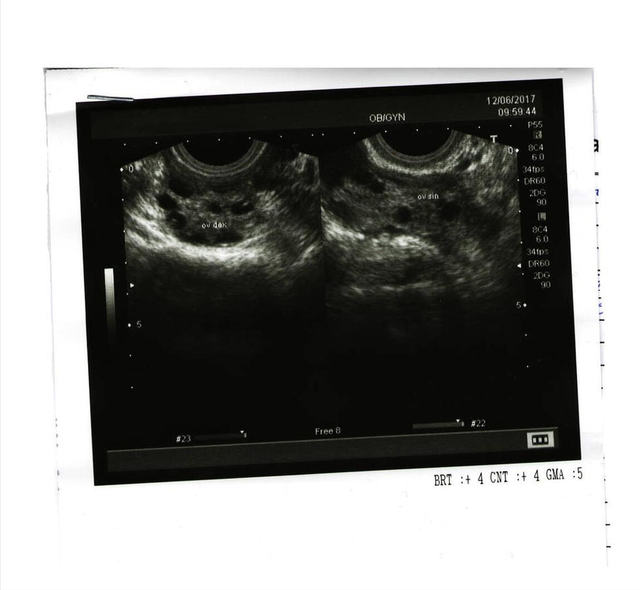

卵巢是位于下腹储备卵子的两个小器官。在月经第一天,其中一个卵巢中已有一个特选卵子正在形成,大概两个星期后,这个逐渐长大的卵子旁边有囊肿包围着它。当排卵期到了,囊肿会破裂爆开,释放卵子。之后,囊肿会在排卵后消失。不过,也有一些囊肿最终没有爆开,反而继续成长。

卵巢囊肿的发病与环境因素、生活习惯、精神状态等有关,但与婚否没有直接关系。未婚女性发现腰围和腹部异常,如有月经失调、经量减少甚至腹痛等症状时,而且持续无好转,应提高警惕。特别是身材偏胖的青少年女性更需注意。主要是因为青春期是卵巢发育成熟、功能旺盛时期,如乱用激素类补品、饮食不当、压力过大,卵巢都极易受到刺激,发生囊肿。对未婚女性来讲,一年一次妇科B超检查十分必要。